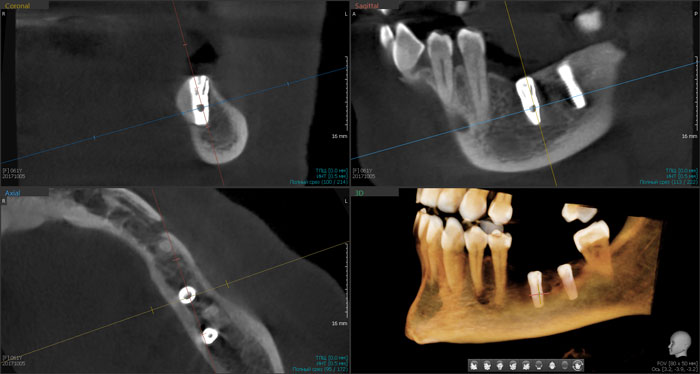

Результаты рентгенологического исследования показали, что дентальная объемная томография наиболее информативный метод при оценке степени повреждения нижнего альвеолярного нерва. Истинное трехмерное изображение исследуемого объекта и вращение его вокруг любой из трех осей на 360 градусов, позволяют визуализировались положение имплантата по отношению к нижнечелюстному каналу и документировать степень его повреждения. Программное обеспечение Ez3D-iV4.3.0 от Vatech предполагает огромный функциональный набор. Применительно к диагностике повреждения нерва после имплантации в данном софте в режиме высокого качества разрешения возможна трехпроекционная реконструкция, с возможностями переориентации осей, с измерением габаритов объекта исследования в масштабе 1:1(рис.3).

Рис.3 Конусно-лучевая компьютерная томография от Vatech. На коронарной проекции определяется верхушка дентального имплантата 3.6, перфорирующая медиальную стенку нижнечелюстного канала.